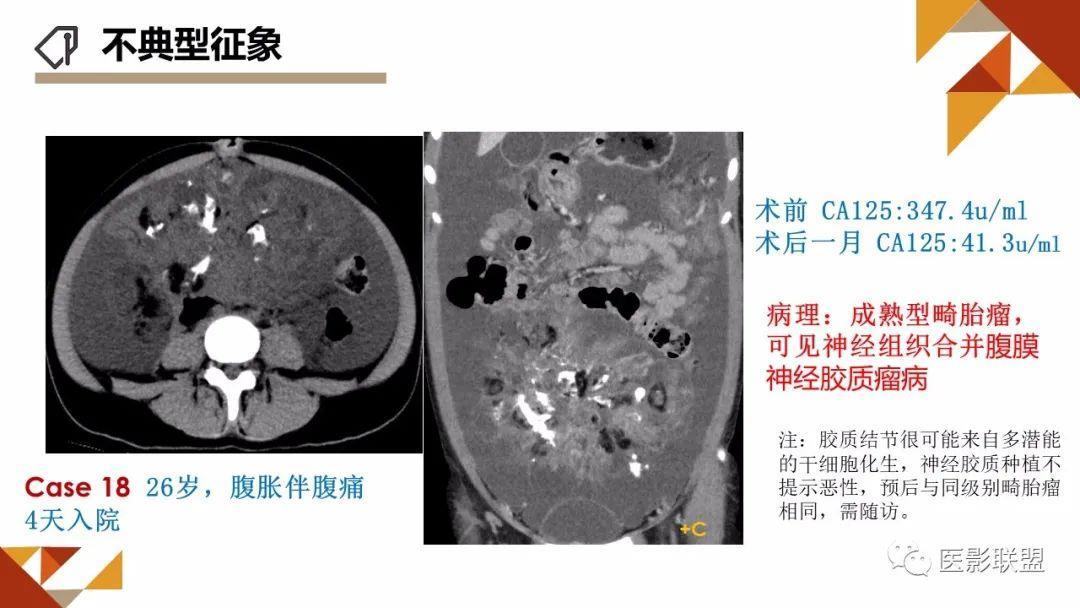

卵巢畸胎瘤的图像诊断及不典型征象分析

作者:刘红艳 清远市人员医院